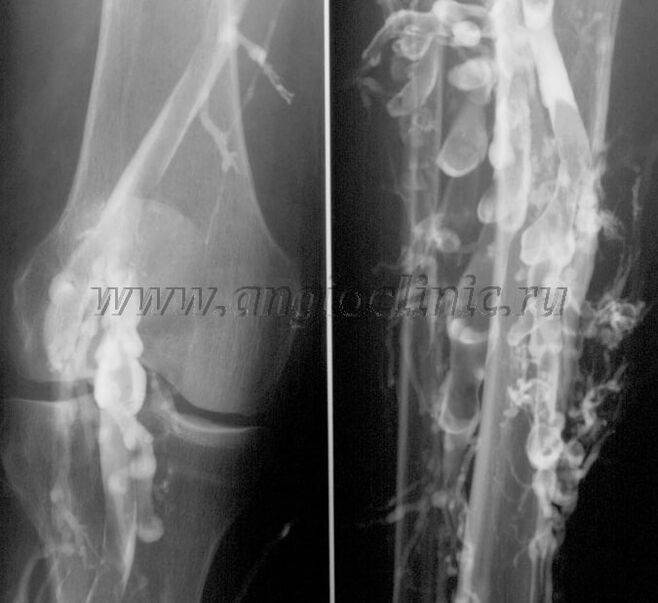

Contrast venography

Kasagaran, ultrasound scan mao ang igo alang sa usa ka bug-os nga pagdayagnos sa ugat patolohiya, apan sa pipila ka mga kaso nga kini mao ang gikinahanglan nga sa pagtuon sa relasyon tali sa kahimtang sa lawom ug taphaw nga ugat nga sistema, ilabi na sa kaso sa pagbalik-balik sa varicose veins ug secondary varicose veins.

Aron masulbad kini nga mga problema, gigamit ang contrast X-ray examination. Ang saphenous nga mga ugat gibuslotan ug ang contrast gihatag. Ang paglihok sa kalainan makita sa monitor sa X-ray machine, ug ang tanan nga gikinahanglan nga mga pagsulay ug mga projection gihimo. Sa pagkakaron, venography alang sa varicose veins gigamit kaayo panagsa ra.